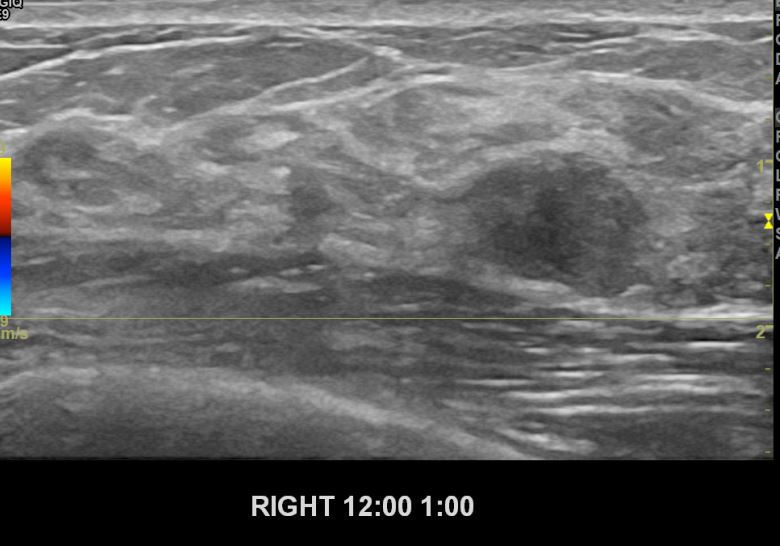

상기환자 유방에 만져지는 멍울로 내원하신 40대 여성분으로

본원 초음파상 우측12시에서1시방향에 의심스러운 멍울 조직검사 시행하여

유방암 진단되었습니다